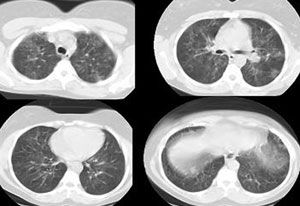

The patient was admitted with a tentative diagnosis of infectious exacerbation of asthma and pneumonia. She was treated with oxygen via nasal cannula (4 L/min); intravenous hydrocortisone, levofloxacin, and metronidazole; nebulized albuterol every 4 hours; and smoking cessation counseling. A pulmonary consultation was requested on day 5 because the patient did not have an appreciable clinical response to therapy. A CT scan of the chest revealed bilateral, diffuse, ground-glass opacities without significant air trapping (Figure 2).

The chest radiographic findings are abnormal in 70% to 80% of cases.5 CT scans and chest radiographs most frequently demonstrate ground-glass opacities that are known to correlate with macrophage accumulation in the alveolar spaces and alveolar ducts.6